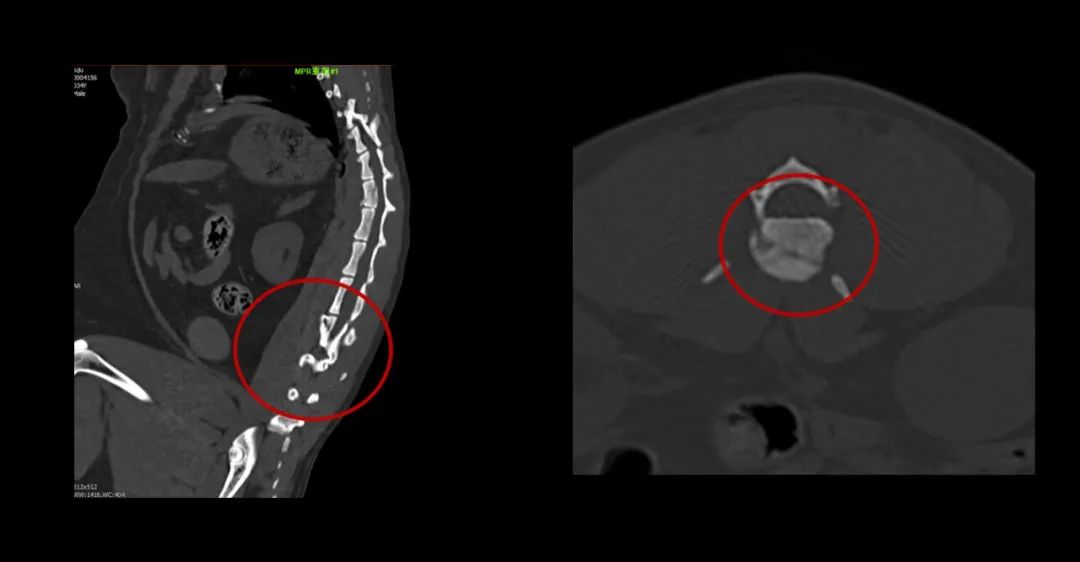

▲俗話說“貓有九條命”,可不能當(dāng)真哦。你看看這兩個(gè)小家伙從樓上高空落地,一只左側(cè)股骨遠(yuǎn)端骨折,另一只第1腰椎椎體骨折。